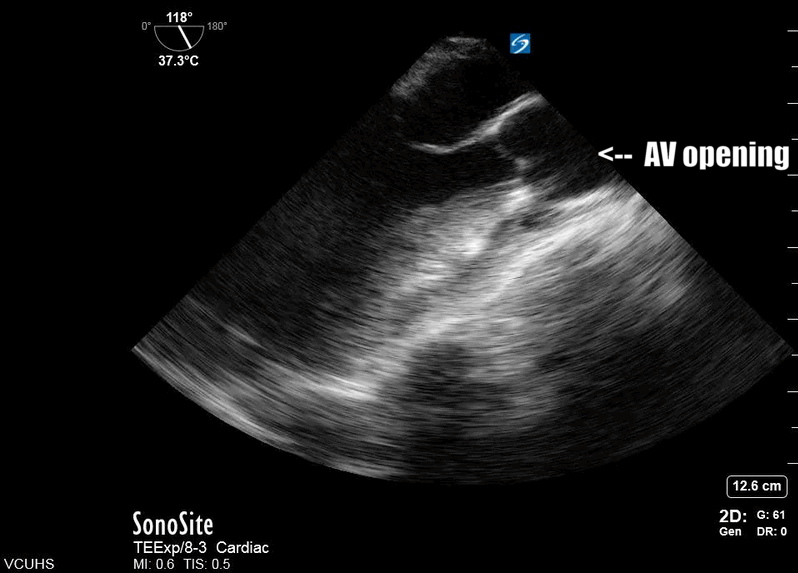

Most importantly for the resuscitationist, the ME-LAX view is used to evaluate the quality of CPR and hand placement for chest compressions; so it should be obtained during initiation of CPR and even when changing CPR providers if possible. Optimal chest compressions should result in vigorous LV squeeze with near concurrent aortic valve opening (Figure 2). Incorrect compressions, usually too high on the chest wall, will result in LV outflow obstruction and ineffective CPR (Figure 3). This can be seen on the ME-LAX view as squeeze over the AV itself, narrowing of the aortic outflow tract, absence of LV compression and/or absence of aortic valve opening during compressions. Signs of ineffective CPR should prompt adjustments in compression location and/or depth and subsequent re-evaluation for effectiveness.2

Figure 2. Me-LAX view during CPR (slowed to 50% speed) showing mid-LV compression with concurrent aortic valve opening